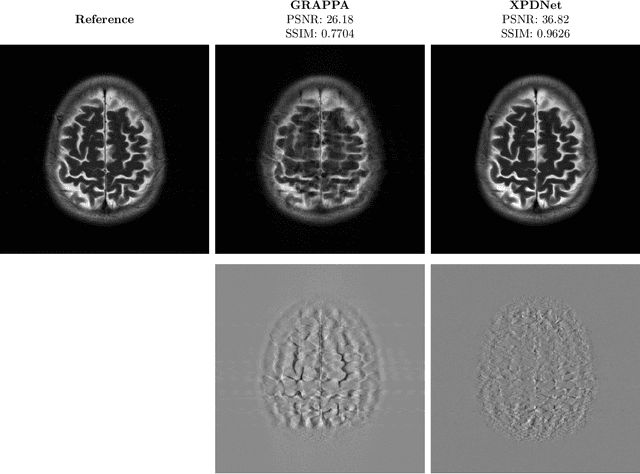

Abstract:We perform a qualitative analysis of performance of XPDNet, a state-of-the-art deep learning approach for MRI reconstruction, compared to GRAPPA, a classical approach. We do this in multiple settings, in particular testing the robustness of the XPDNet to unseen settings, and show that the XPDNet can to some degree generalize well.

Abstract:We present a modular cross-domain neural network the XPDNet and its application to the MRI reconstruction task. This approach consists in unrolling the PDHG algorithm as well as learning the acceleration scheme between steps. We also adopt state-of-the-art techniques specific to Deep Learning for MRI reconstruction. At the time of writing, this approach is the best performer in PSNR on the fastMRI leaderboards for both knee and brain at acceleration factor 4.